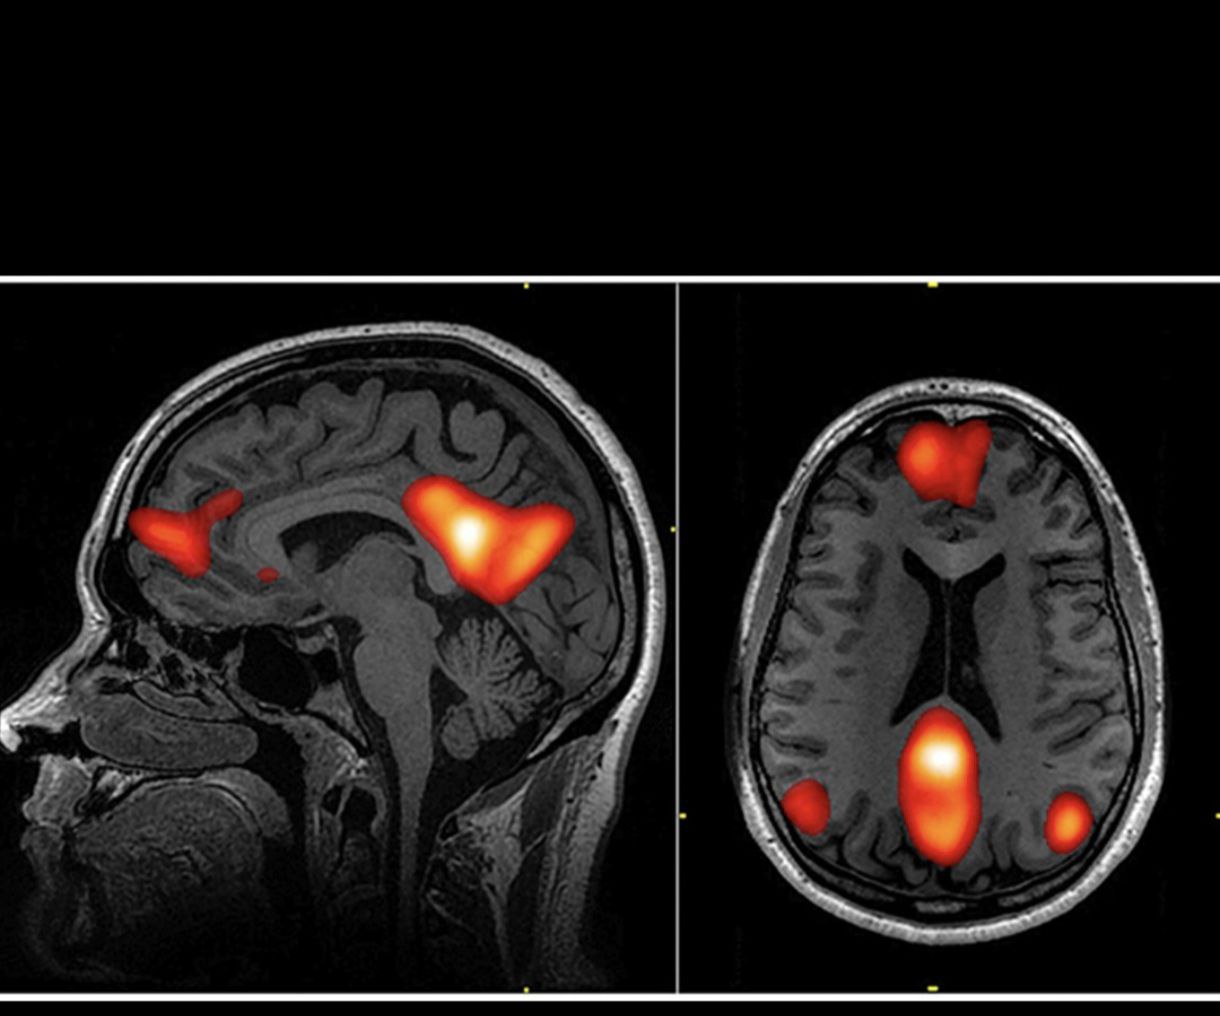

Дослідження 2016 року, проведене доктором Майклом Фергюсоном за допомогою фМРТ-сканування, показало, що поклоніння активує унікальну комбінацію ділянок мозку – систему винагороди, центри морального мислення та мережі зосередженої уваги – всі вони працюють разом за схемою, яку ніщо інше не відтворює.

Любов, музика, краса – вони запалюють частини мозку.

Але поклоніння? Воно задіює всі три системи одночасно.

Воно має неврологічні особливості. Ось чому люди описують його, як щось зовсім інше – бо це так.